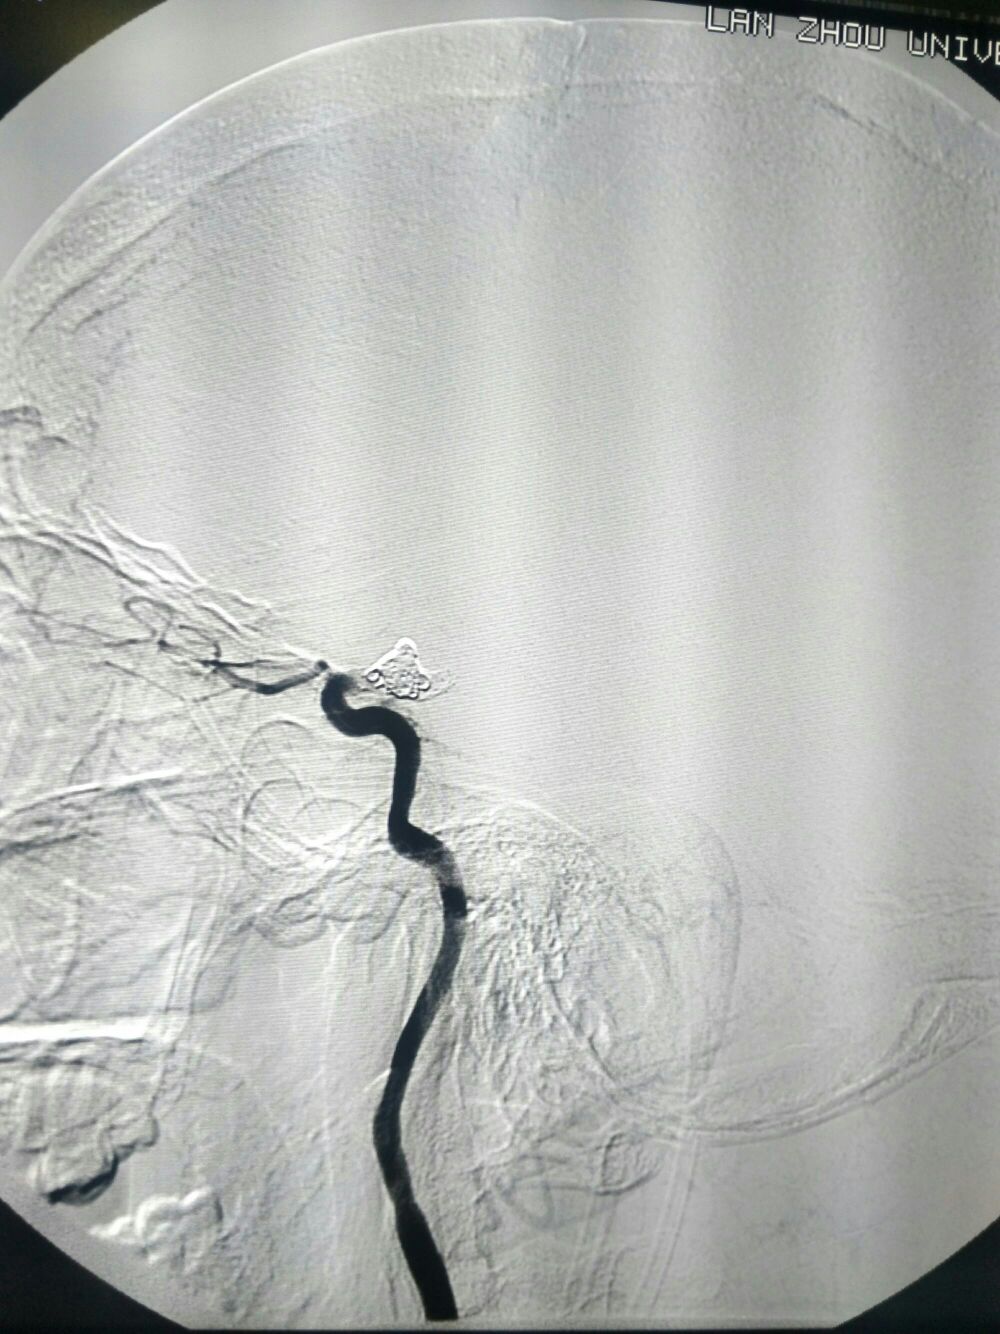

DSA左侧ICA“血泡”样动脉瘤

动脉瘤大小5.5*8mm

手术方案:双支架+弹簧圈+打补定致密栓塞

栓塞工作角度33/-28影像满意